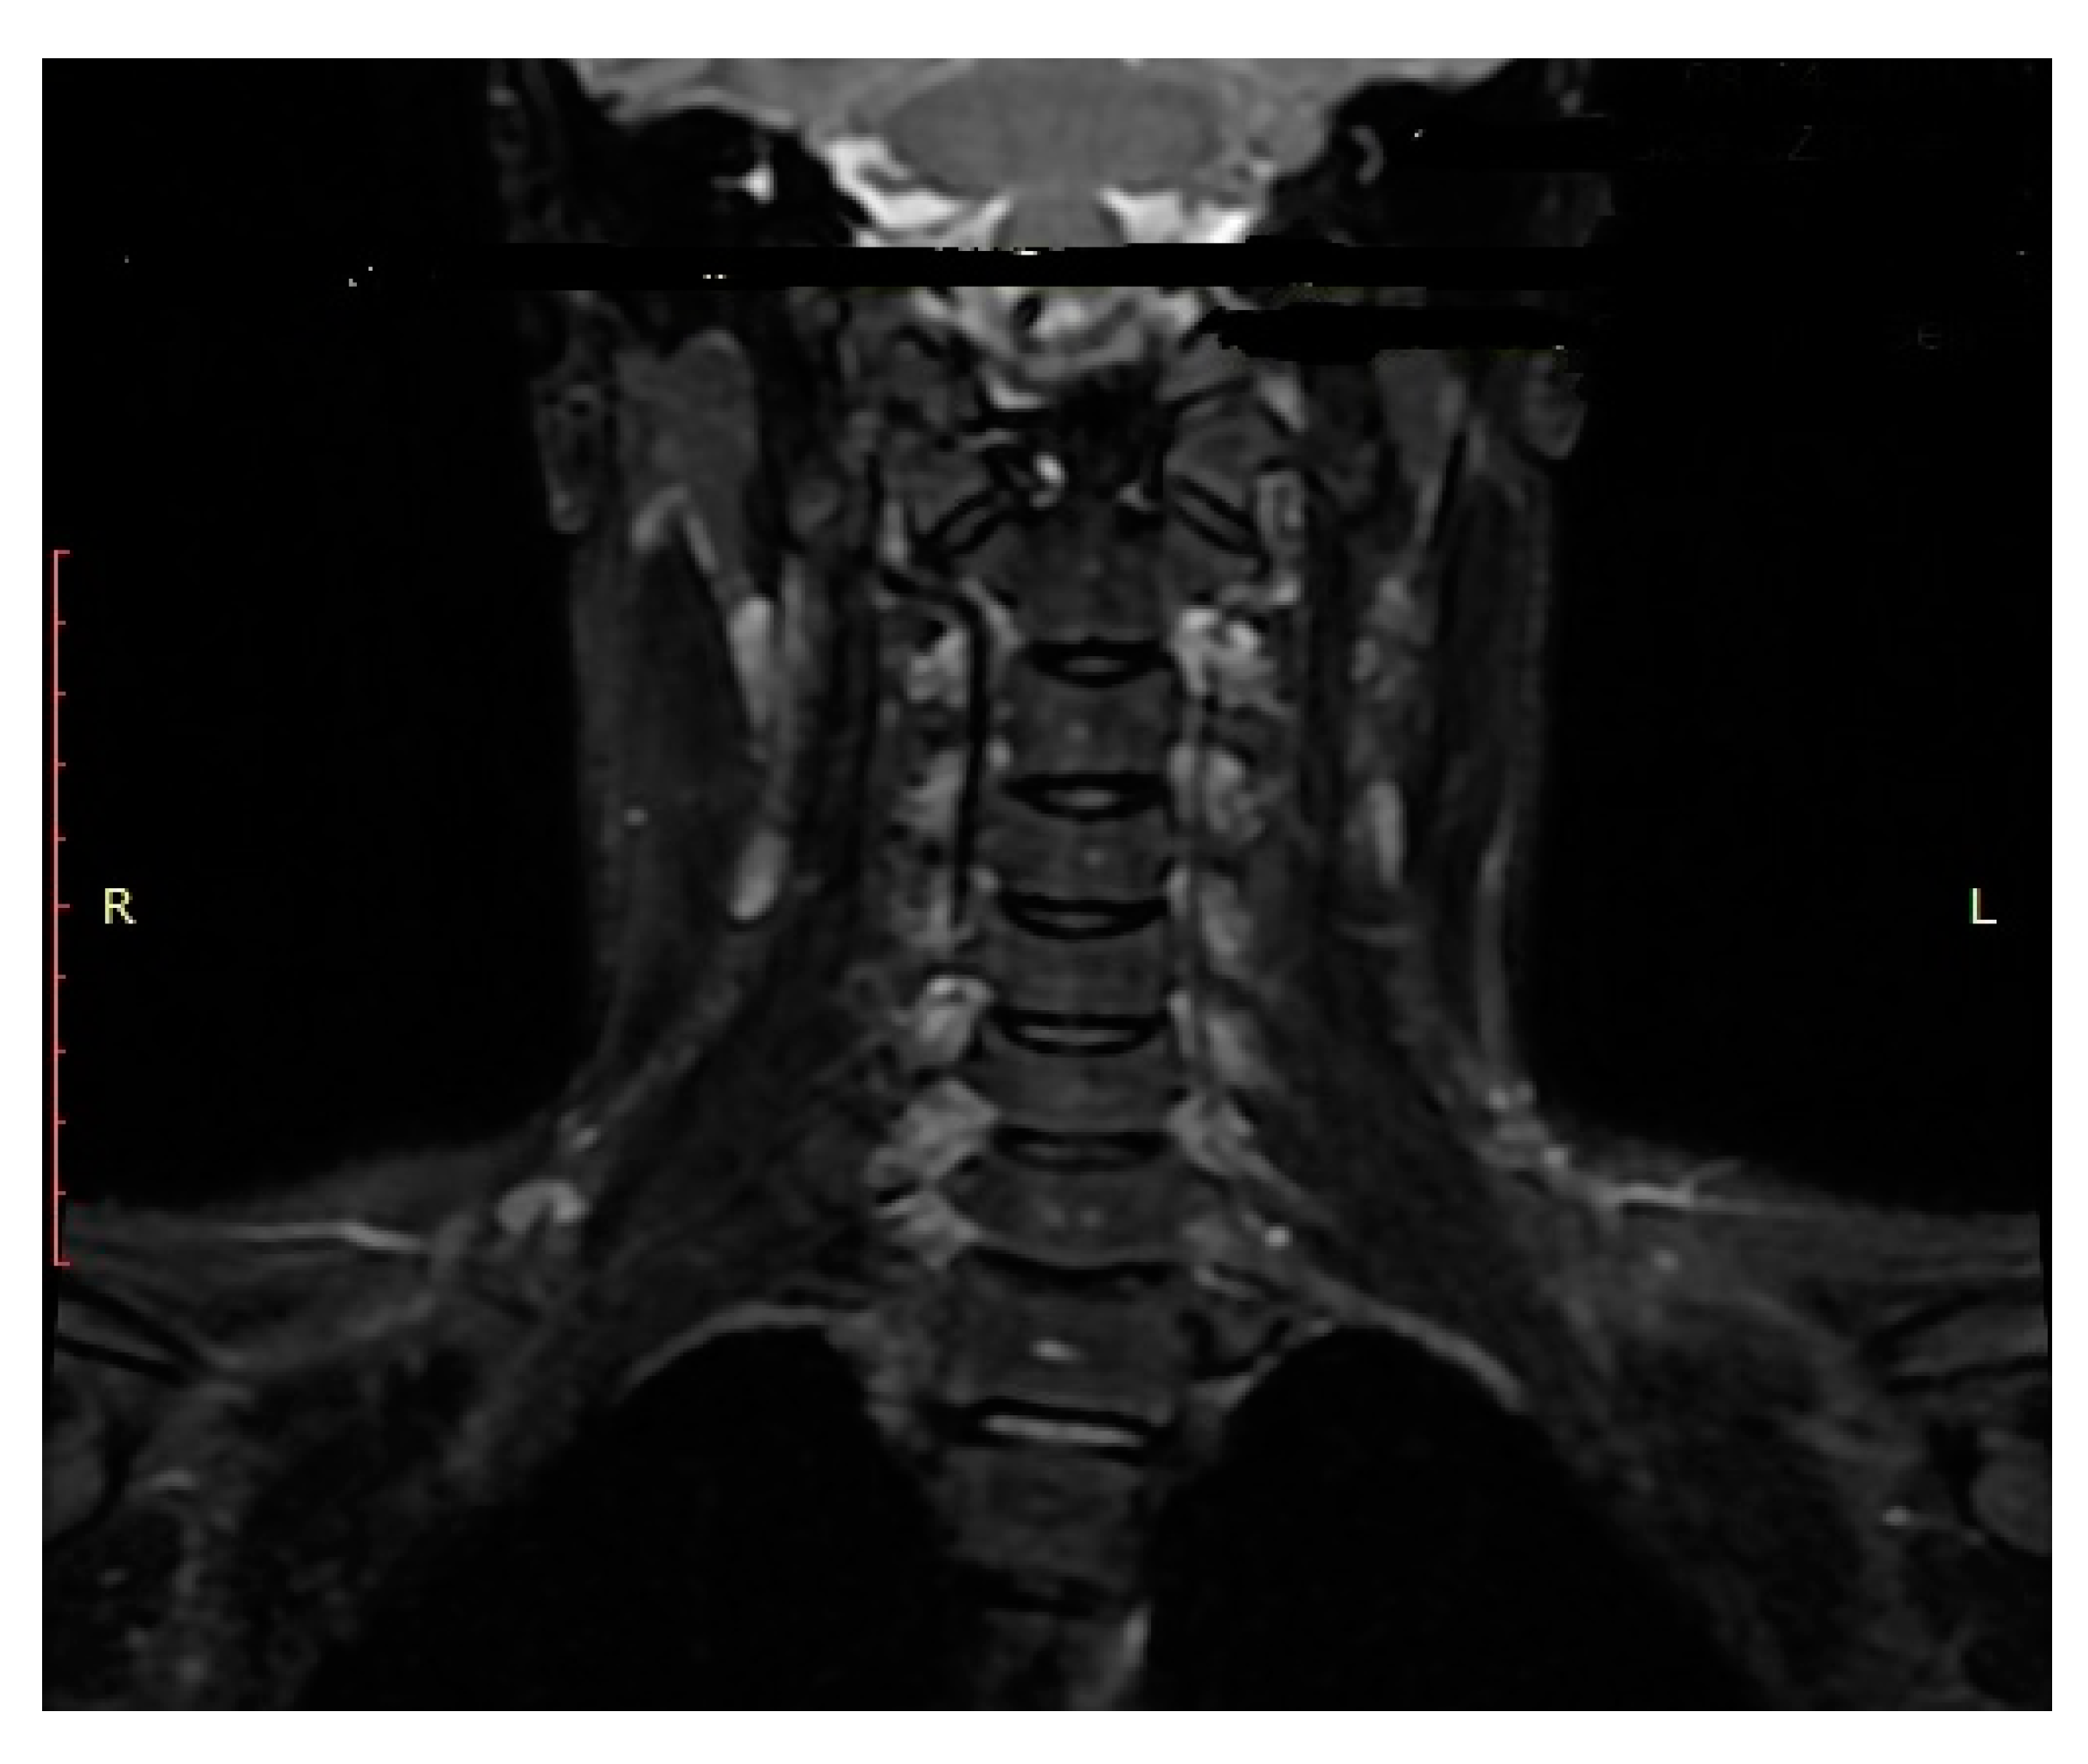

- We recommend CT and MRI of the CCJ to diagnose OCF and confirm post-therapeutic fracture consolidation in pediatric patients.

- Roy, A.K.; Miller, B.A.; Holland, C.M.; Fountain, A.J.; Pradilla, G.; Ahmad, F.U. Magnetic resonance imaging of traumatic injury to the craniovertebral junction: A case-based review. Neurosurg. Focus 2015, 38, E3. [Google Scholar] [CrossRef]

| Name (Initials) | Sex (Male/ Female) | Age (Years) | Anderson Montesano Classification | Tuli Classification | Cause of Injury | Accompanying Injuries | Immobilization Method |

|---|---|---|---|---|---|---|---|

| P.P. | M | 15.2 | III (unstable) | IIB | Road traffic accident (car passenger) | Fracture frontal bone, fracture frontal sinus, contusion of frontal lobe | Halo-vest immobilization: 12.5 weeks |

| K.D. | F | 15 | III (unstable) | IIB | Pedestrian hit by car | Lung contusion, brain concussion, multiple abrasions | Halo-vest immobilization: 13 weeks |

| R.M. | F | 18 | I (unstable) | IIB | Road traffic accident (car passenger) | Pneumothorax, neurogenic vocal cord injury, post-traumatic aphasia | Halo-vest immobilization: 14 weeks |

| S.D. | M | 14.7 | III (stable) | IIA | Road traffic accident (car passenger) | Fracture of frontal bone, fracture of nasal bone, subdural hematoma | Minerva-brace immobilization |

| B.W. | F | 16 | I (stable) | IIA | Fall from a height | Fracture of frontal bone, fracture of nasal bone, subarachnoid hemorrhage, fracture of transverse process Th3-5, fracture of radius | Minerva-brace immobilization |

| M.O. | M | 16.1 | I (stable) | IIA | Bicycle incident | Fracture frontal bone, fracture maxillary sinus, fracture orbit, metacarpal fracture | Minerva-brace immobilization |